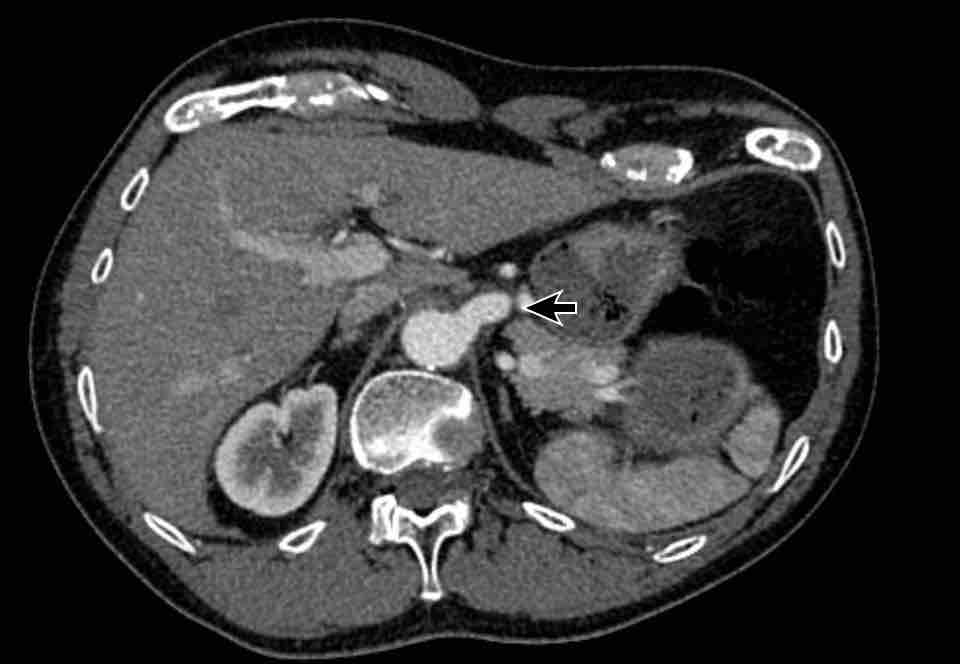

Hình ảnh

Bệnh nhân này được lên kế hoạch cắt thùy trên phải do ung thư phổi và bất thường mạch máu này ban đầu đã bị bỏ sót trên hình ảnh CT.

Những hệ quả trong phẫu thuật của bất thường như vậy nhấn mạnh tầm quan trọng của việc không bỏ sót các biến thể này.